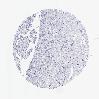

KIDNEY RENAL PAPILLARY CELL CARCINOMA (TCGA) - Interactive survival scatter ploti

The Survival Scatter plot shows the clinical status (i.e. dead or alive) for all individuals in the patient cohort, based on the same data that underlies the corresponding Kaplan-Meier plots. Patients that are alive at last time for follow-up are shown in blue and patients who have died during the study are shown in red.

The x-axis shows the expression levels (FPKM) of the investigated gene in the tumor tissue at the time of diagnosis. The y-axis shows the follow-up time after diagnosis (years). Both axes are complimented with kernel density curves demonstrating the data density over the axes. The top density plot shows the expression levels (FPKM) distribution among dead (red) and alive patients (blue). The right density plot shows the data density of the survived years of dead patients with high and low expression levels respectively, stratified using the cutoff indicated by the vertical dashed line through the Survival Scatter plot. This cutoff is automatically defined based on the FPKM cutoff that minimizes the p-score. The cutoff can be changed by dragging the vertical line or by entering a cutoff value in the square labeled "Current cut-off".

Under the Survival Scatter plot the p-score landscape (black curve; left axis) is shown together with dead median separation (red curve; right axis). Dead median separation is the difference in median mRNA expression between patients who have died with high and low expression, respectively. It is calculated as follows: median FPKM expression of dead patients with high expression - median FPKM expression of dead patients with low expression. This is intended to aid the user in visually exploring custom cutoffs and the associated p-scores and dead median separation.

Individual patient data is displayed and can be filtered by clicking on one or more of the category buttons on the top of the page. Categories describing expression level and patient information include: high, low, alive, dead, female, male and tumor stages. The scale of the x-axis can be toggled between linear and log-scale by clicking on the "x log" button. Mouse-over function shows TCGA ID, patient information and mRNA expression (FPKM) for each patient.

& Survival analysisi

Kaplan-Meier plots summarize results from analysis of correlation between mRNA expression level and patient survival. Patients were divided based on level of expression into one of the two groups "low" (under cut off) or "high" (over cut off). X-axis shows time for survival (years) and y-axis shows the probability of survival, where 1.0 corresponds to 100 percent.

GZMB is not prognostic in Kidney Renal Papillary Cell Carcinoma (TCGA)